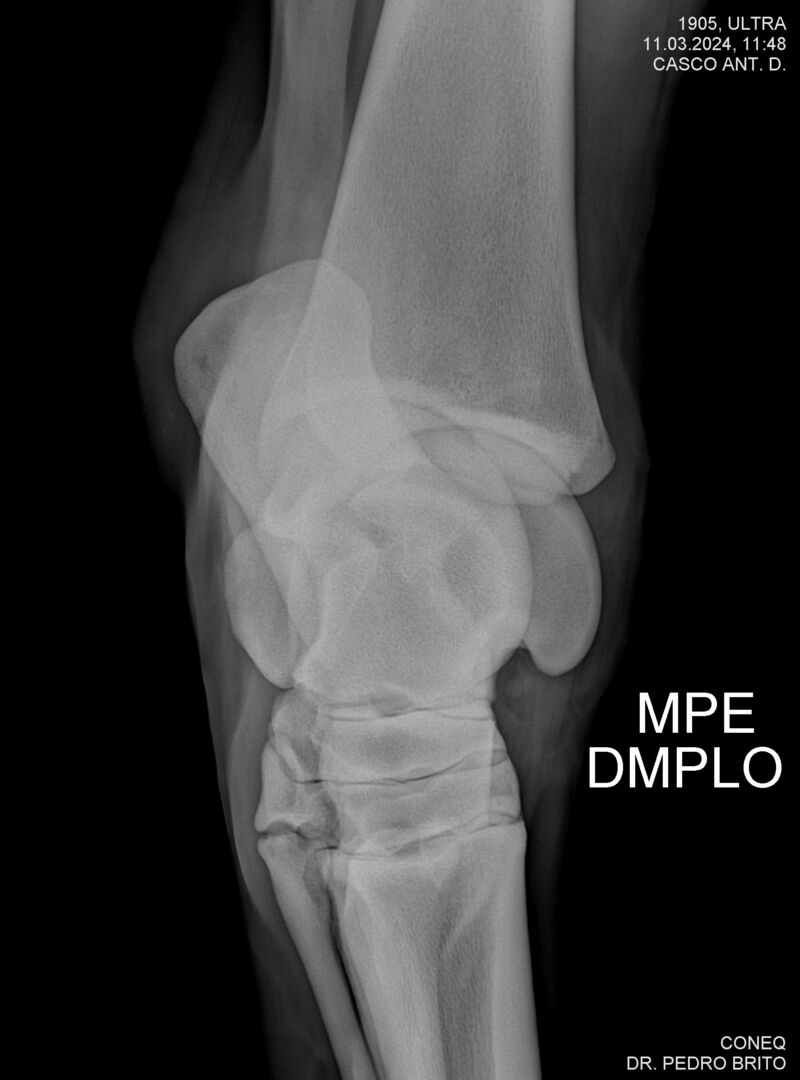

ULTRA DO CACH

Raça: BRASILEIRO DE HIPISMO

Sexo: CASTRADO - CASTRADO

Nascimento: 22/11/2020

Altura Aproximada: 1,67

Pel.: CASTANHO

Registro: 25966-BH

Vend.: HARAS CACHOEIRINHA

Local : PIRASSUNUNGA/SP